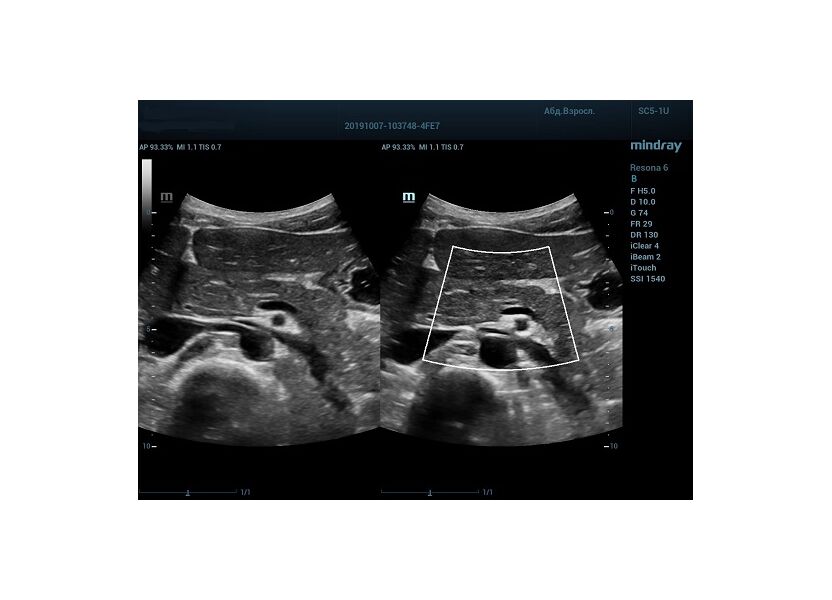

HD Scope позволяет достигать поразительной разрешающей способности выбранной зоны сканирования, при этом улучшая как детализацию, так и контрастность изображения. Помимо пространственного разрешения мы получаем преимущество и по разрешению во времени. Прибор получает огромное количество нативных изображений практически одновременно, и при сборе итоговой картины не происходит смещения объекта под датчиком, а значит и нет размывания изображения. Все участки раздела фаз, каждый контур образования теперь видны, мы все ближе к идеальной картинке.